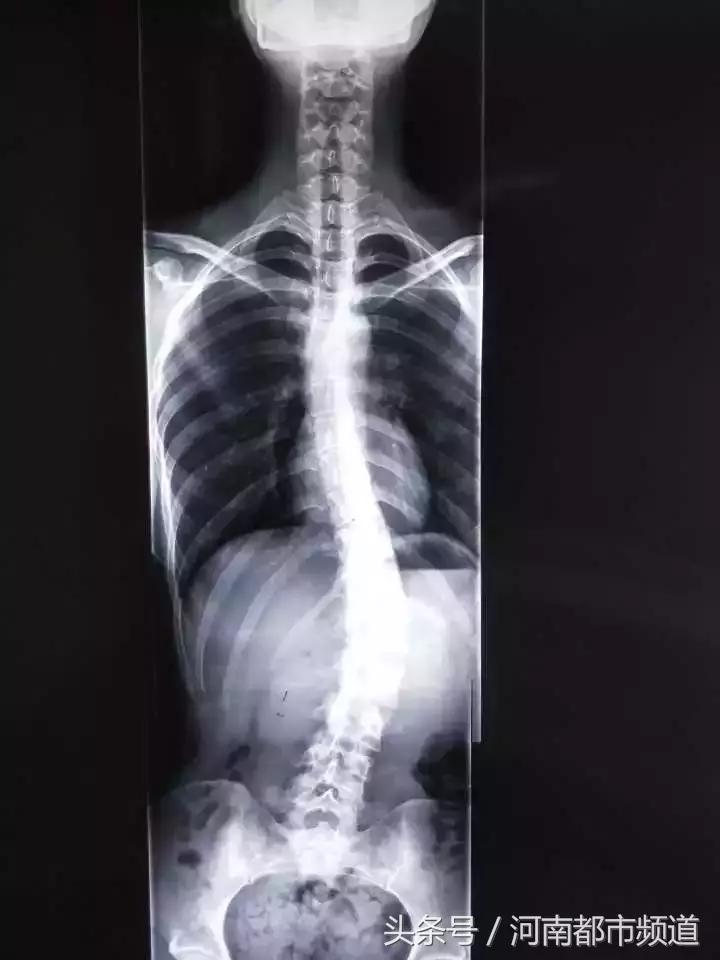

林女士的女儿也是23岁,在上海念大四,也有脊柱侧弯,上衣撩起来,腰部左侧明显比右侧高,X片里,脊柱呈现一个C型。“说是青春期的毛病,现在矫正来不及了,要是开刀,得在脊柱上打钉子,被钉子‘钉着’过一辈子,太遭罪了!”

“腰左侧高,脊柱往右边弯了。”他再仔细查看了X片,接着往下说,“小姑娘侧弯的度数还是比较厉害的,Cobb角已经超过30°了。”

目前脊柱侧弯测量多选择Cobb角,如果超过10°,就需要引起重视。

国际脊柱侧弯研究学会提出:应用Cobb角法测量,站立正位X线片的脊柱侧方弯曲,大于10度为脊柱侧弯,大于25度就必须进行支具治疗,而大于40度时就已具备手术指征。